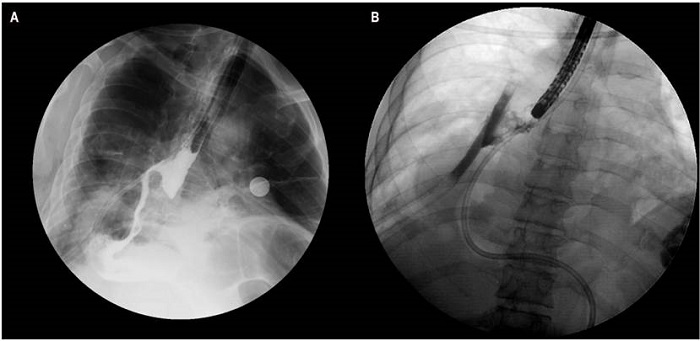

Hombre de 69 años con antecedente de adenocarcinoma gástrico, con extensión a la unión gastroesofágica, estadificado III b (pT4N0M0), con antecedente de diabetes mellitus. El paciente se llevó a esofagogastrectomía por laparoscopia y toracoscopia con bordes de sección negativos, en manejo con adyuvancia y protocolo Capeox. Presentó disfagia orofaríngea y odinofagia, así como pérdida de peso de 18 kg. En el día 11 posoperatorio presenta signos de respuesta inflamatoria, con esofagograma, que evidenció una fístula a nivel de anastomosis. El estudio endoscópico mostró hallazgo de fístula de 15 mm en la anastomosis a los 30 cm de las arcadas dentarias; bajo visión fluoroscópica presentó extraluminización fuera de la pared esofágica (Figura 1). El manejo inicial consistió en la colocación de 5 clips. Debido a la friabilidad de la mucosa no se logró el cierre total del defecto.